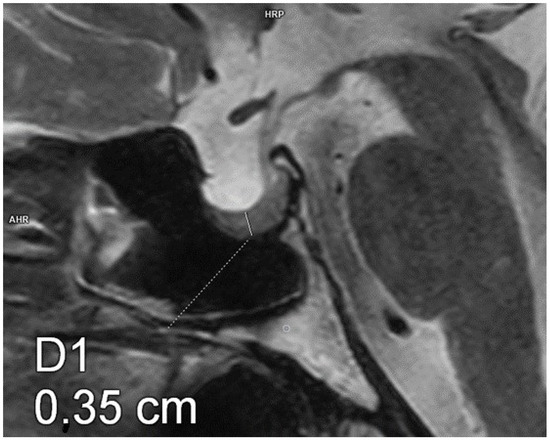

Figure 2.

Partial empty sella. Magnetic resonance imaging, T2-weighted image, sagittal plane. The craniocaudal diameter of the pituitary gland is 3.5 mm.